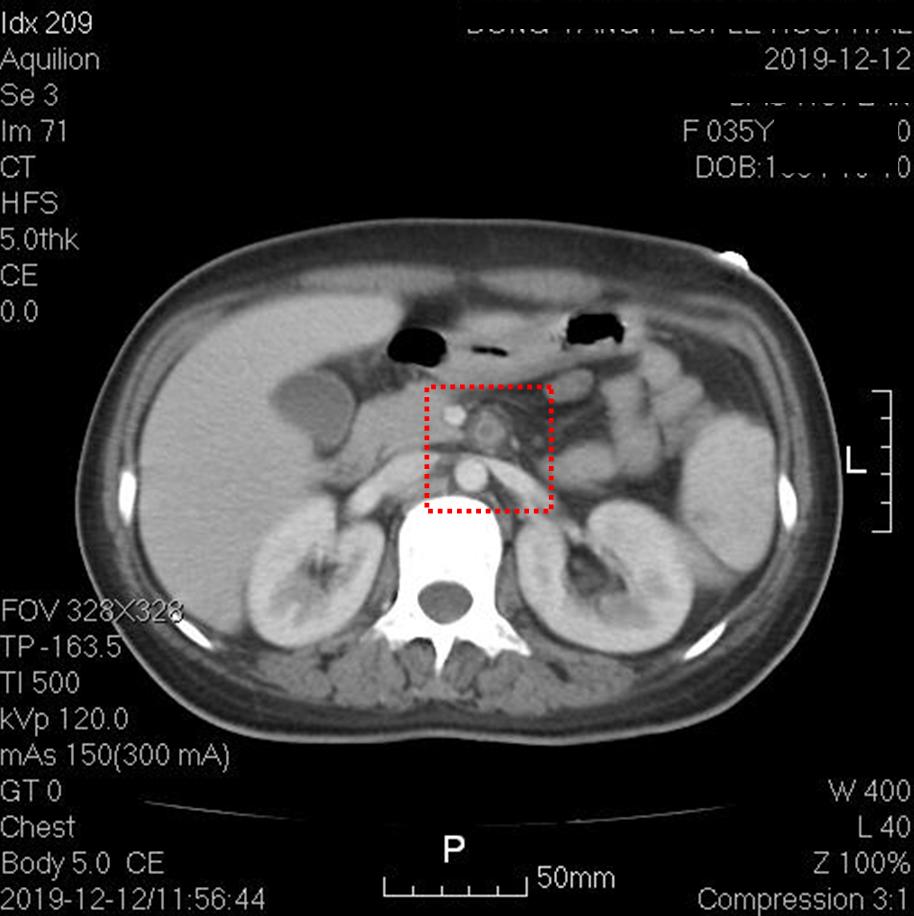

上图红框内为肠系膜上动脉根部,可见管腔内未增强,动脉周边组织稍模糊,提示存在炎症改变。其他层面肠系膜上动脉通畅。

上图红框内为右髂总动脉,可见一段长约2.5厘米的管腔闭塞。